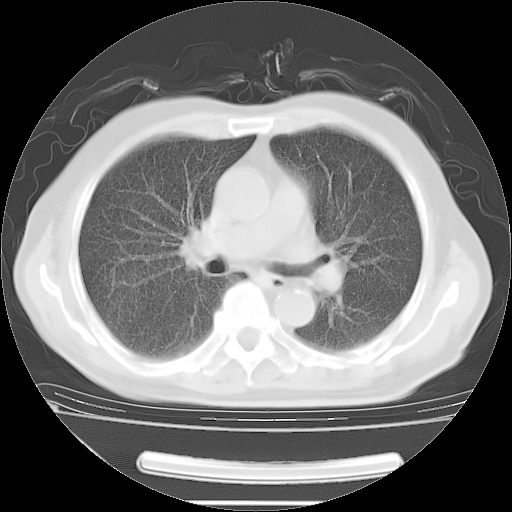

今天复查肺部CT,发现双肺广泛磨玻璃样改变。所以我把3月19日和5月9日相隔50天的肺部CT上传。请大家会诊。

2009年3月19日肺部CT片。

2009年3月19日肺部CT